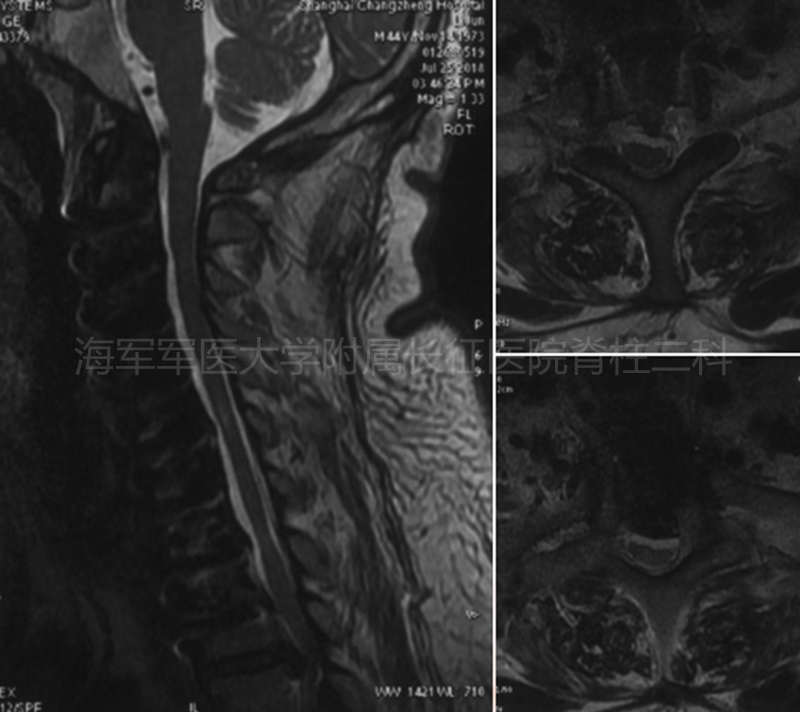

术后侧位平片矢状位MRI和矢状位、水平位CT

术前术后矢状位MRI对比

术后MRI